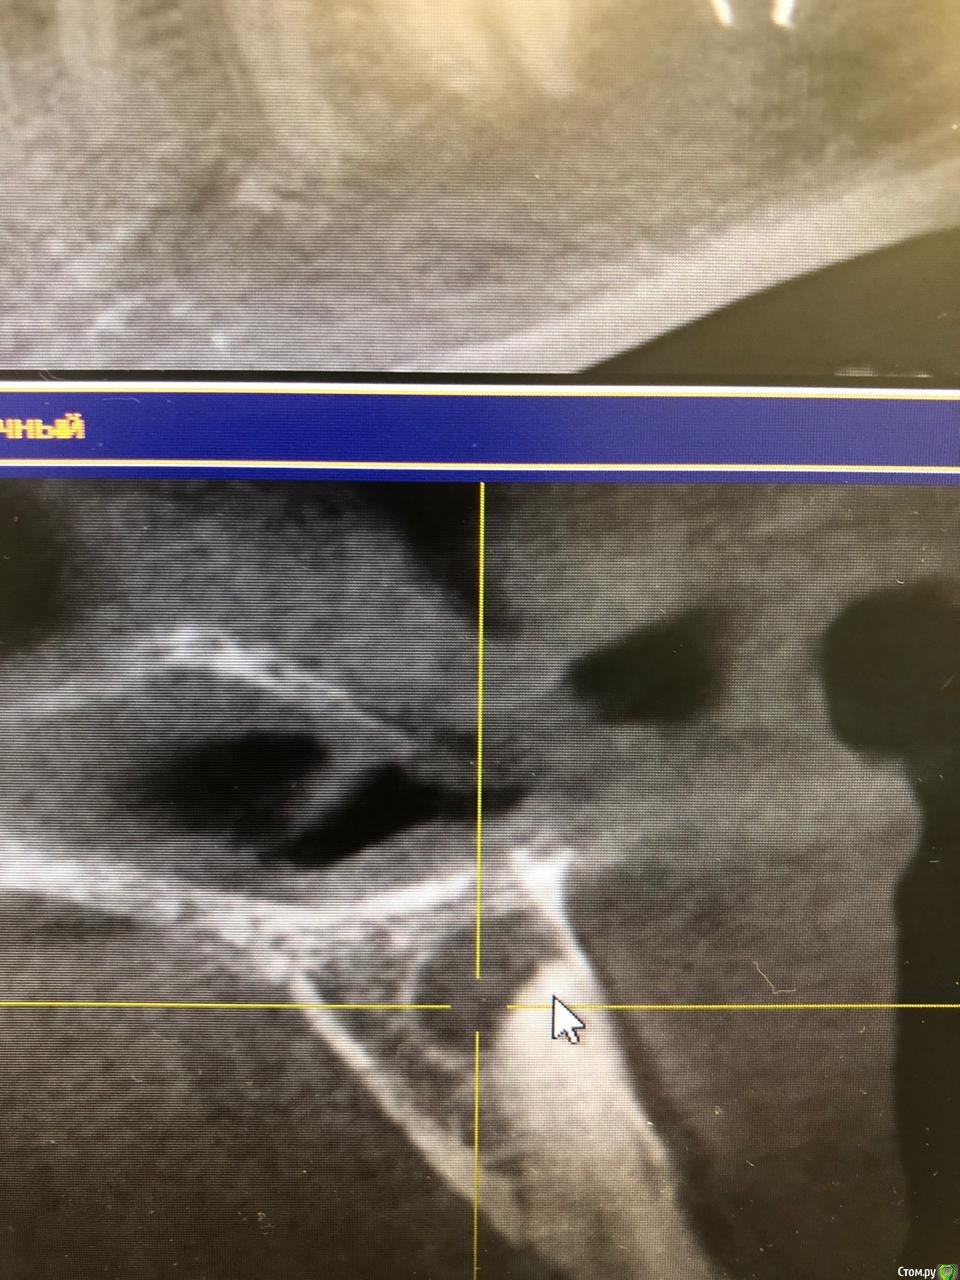

КТ (там и свежее и более старое -2017 года)

2. Давно беспокоил передний справа зуб, вы еще на консультации говорили, что нужно ставить лекарство и ходить с ним... остальные врачи проигнорировали.. .Ортодонт посмотрел КТ и сказал никаких брекетов - за зубом киста, сказала идти к терапевту.

Вскрыла зуб (канал?) убрала мертвый нерв и заложила лекарство. сказала поговорит с хирургом.  но наткнулся на нескольких форумах, что успешно лечат с микроскопом, и на передних нужно побороться..... что делать? :((  ( лекарство заложила и закрыла временной пл в прошлую среду, сказала в эту среду прийти менять лекарство)

Добрый день. Удалять не нужно!  Необходимо найти доктора который сможет хорошо помыть и почистить канал где раньше был нерв и  его запломбировать постоянным материалом, дальше через 6 мес.первый рентген контроль. Если заживает, то все ок, можно брекеты. Если нет и беспокоит то рассматривается вопрос резекции верхушки корня, когда хирург чисти за пределами корня. Зуб при этом остается на месте.